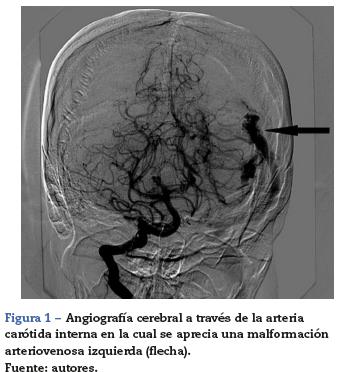

Reportamos el manejo anestésico de una mujer de 32 años con 22 semanas de gestación, quien presentó hemorragia intracraneana (HIC) a causa de la rotura de una malformación arteriovenosa (MAV) (fig. 1). La decisión de un equipo médico multidisciplinario fue realizar la craneotomía a fin de resecar la MAV bajo anestesia general.

La angiografía cerebral reveló una MAV izquierda con vasos alimentadores de las arterias cerebral media y cerebral posterior izquierdas, y drenaje venoso a través del seno transverso superior (fig. 1).